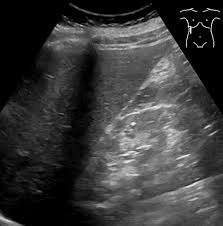

복부 초음파는 인체의 복부 부위에 위치한 장기들을 고해상도 초음파로 들여다보는 비침습적 영상 검사입니다. 방사선 노출이 없고, 검사 시간이 짧으며, 비교적 저렴한 비용으로 복부 초음파로 알 수 있는 것이 많다는 장점 덕분에 다양한 복부 질환의 선별과 진단에 널리 사용됩니다.

특히, 복통·복부 팽만·소화불량·황달 등의 증상 원인을 확인하거나 건강검진 목적으로 시행되기도 하며, 만성 질환자의 정기적인 추적검사 도구로도 쓰입니다.

이처럼 복부 초음파는 단순히 '보는 검사'가 아니라, 질병을 빠르게 감별하거나 중대한 병변 여부를 스크리닝하는 데 필수적인 검사입니다.